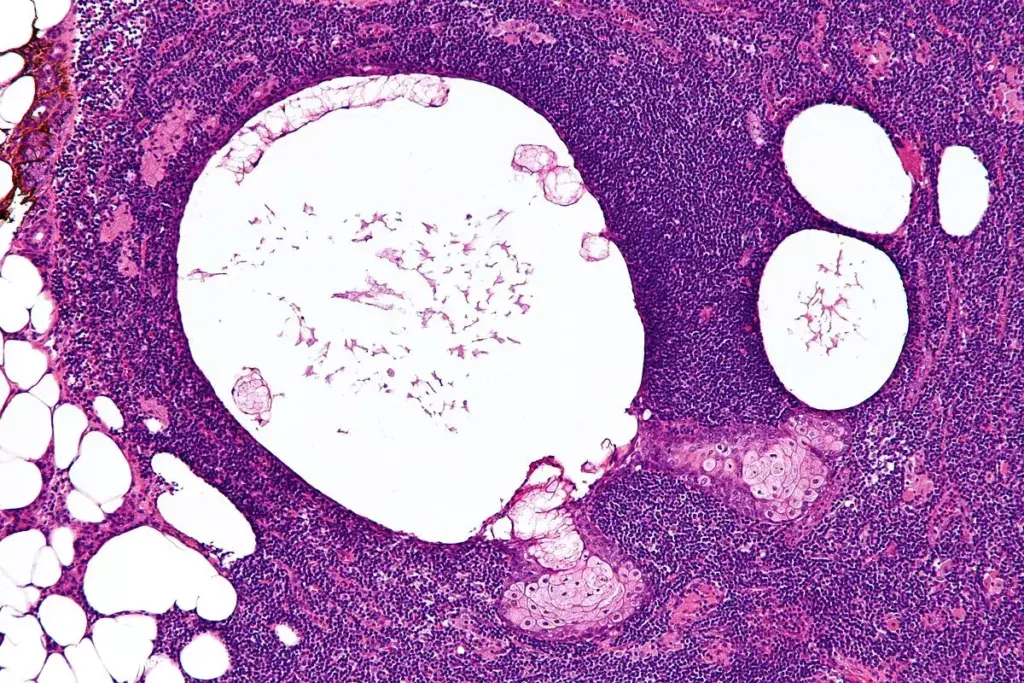

• AIN is a significant cause of acute kidney injury, often diagnosed through renal biopsy.

AIN is an inflammation of the kidney’s interstitium, the area around the tubules. It often starts as an allergic reaction or immune response to medications, infections, or autoimmune disorders. This reaction causes inflammation and damage to the kidney’s interstitium.

AIN is not very common, making up about 1% to 3% of all kidney biopsies. But, it’s a big problem in certain groups, like the elderly and those with many health issues. It’s a key cause of sudden kidney injury, making quick diagnosis and treatment very important.